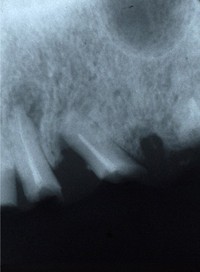

根の先に病巣(病変)があります

根の中の治療(根管治療)を行い病巣も消失しました。